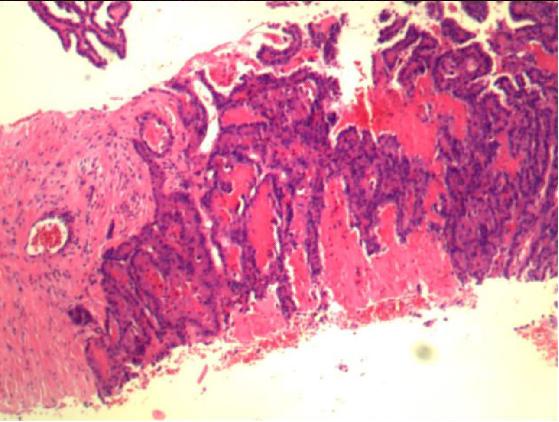

穿刺病理报告

(右侧甲状腺)倾向乳头状癌。 建议标记CK19 , MC , Galectin-3 , CD56 , Tg , TTF-1。

(右颈淋巴结)镜下见乳头状结构的肿瘤/病变。建议标记Tg , TTF-1 , Galectin-3 , CD56 , MC , CK19 , Ki-6